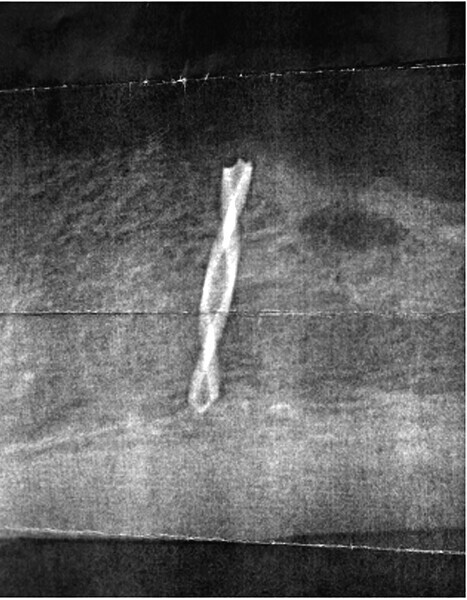

Fig. 6: Reveals the broken pilot drill ‘in the bone’.